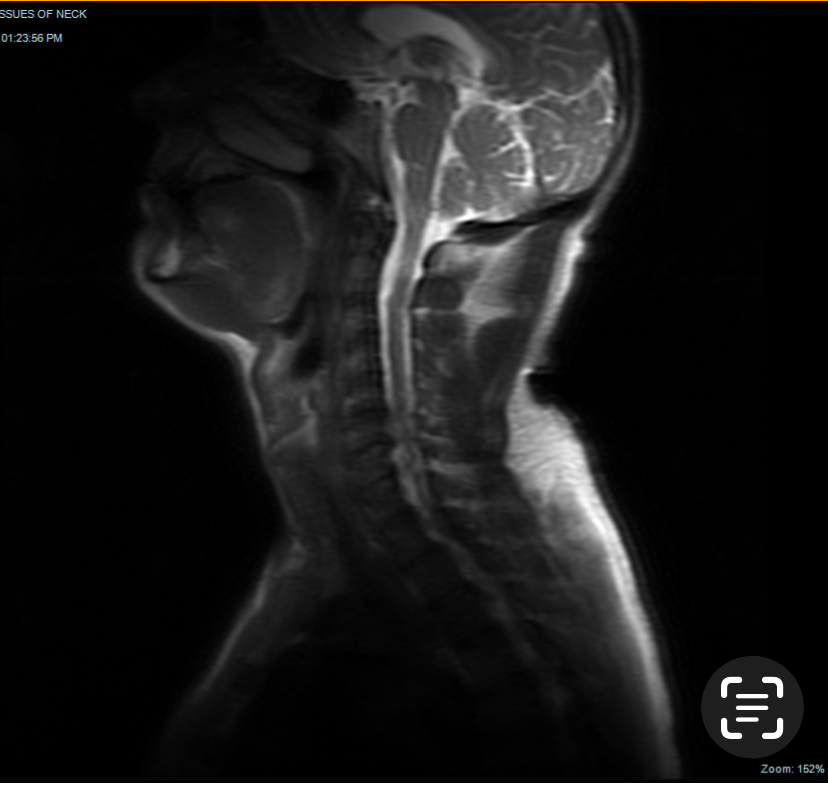

Above photo and imaging show a man with a neck with TMJ &facial muscle (platysma)hardening.

The imaging shows calcification under the teeth in both scans.

The crazy part is that one scan is a dental surgeon scan,The other is a scan done from a request from a GP looking for other spinal injuries.